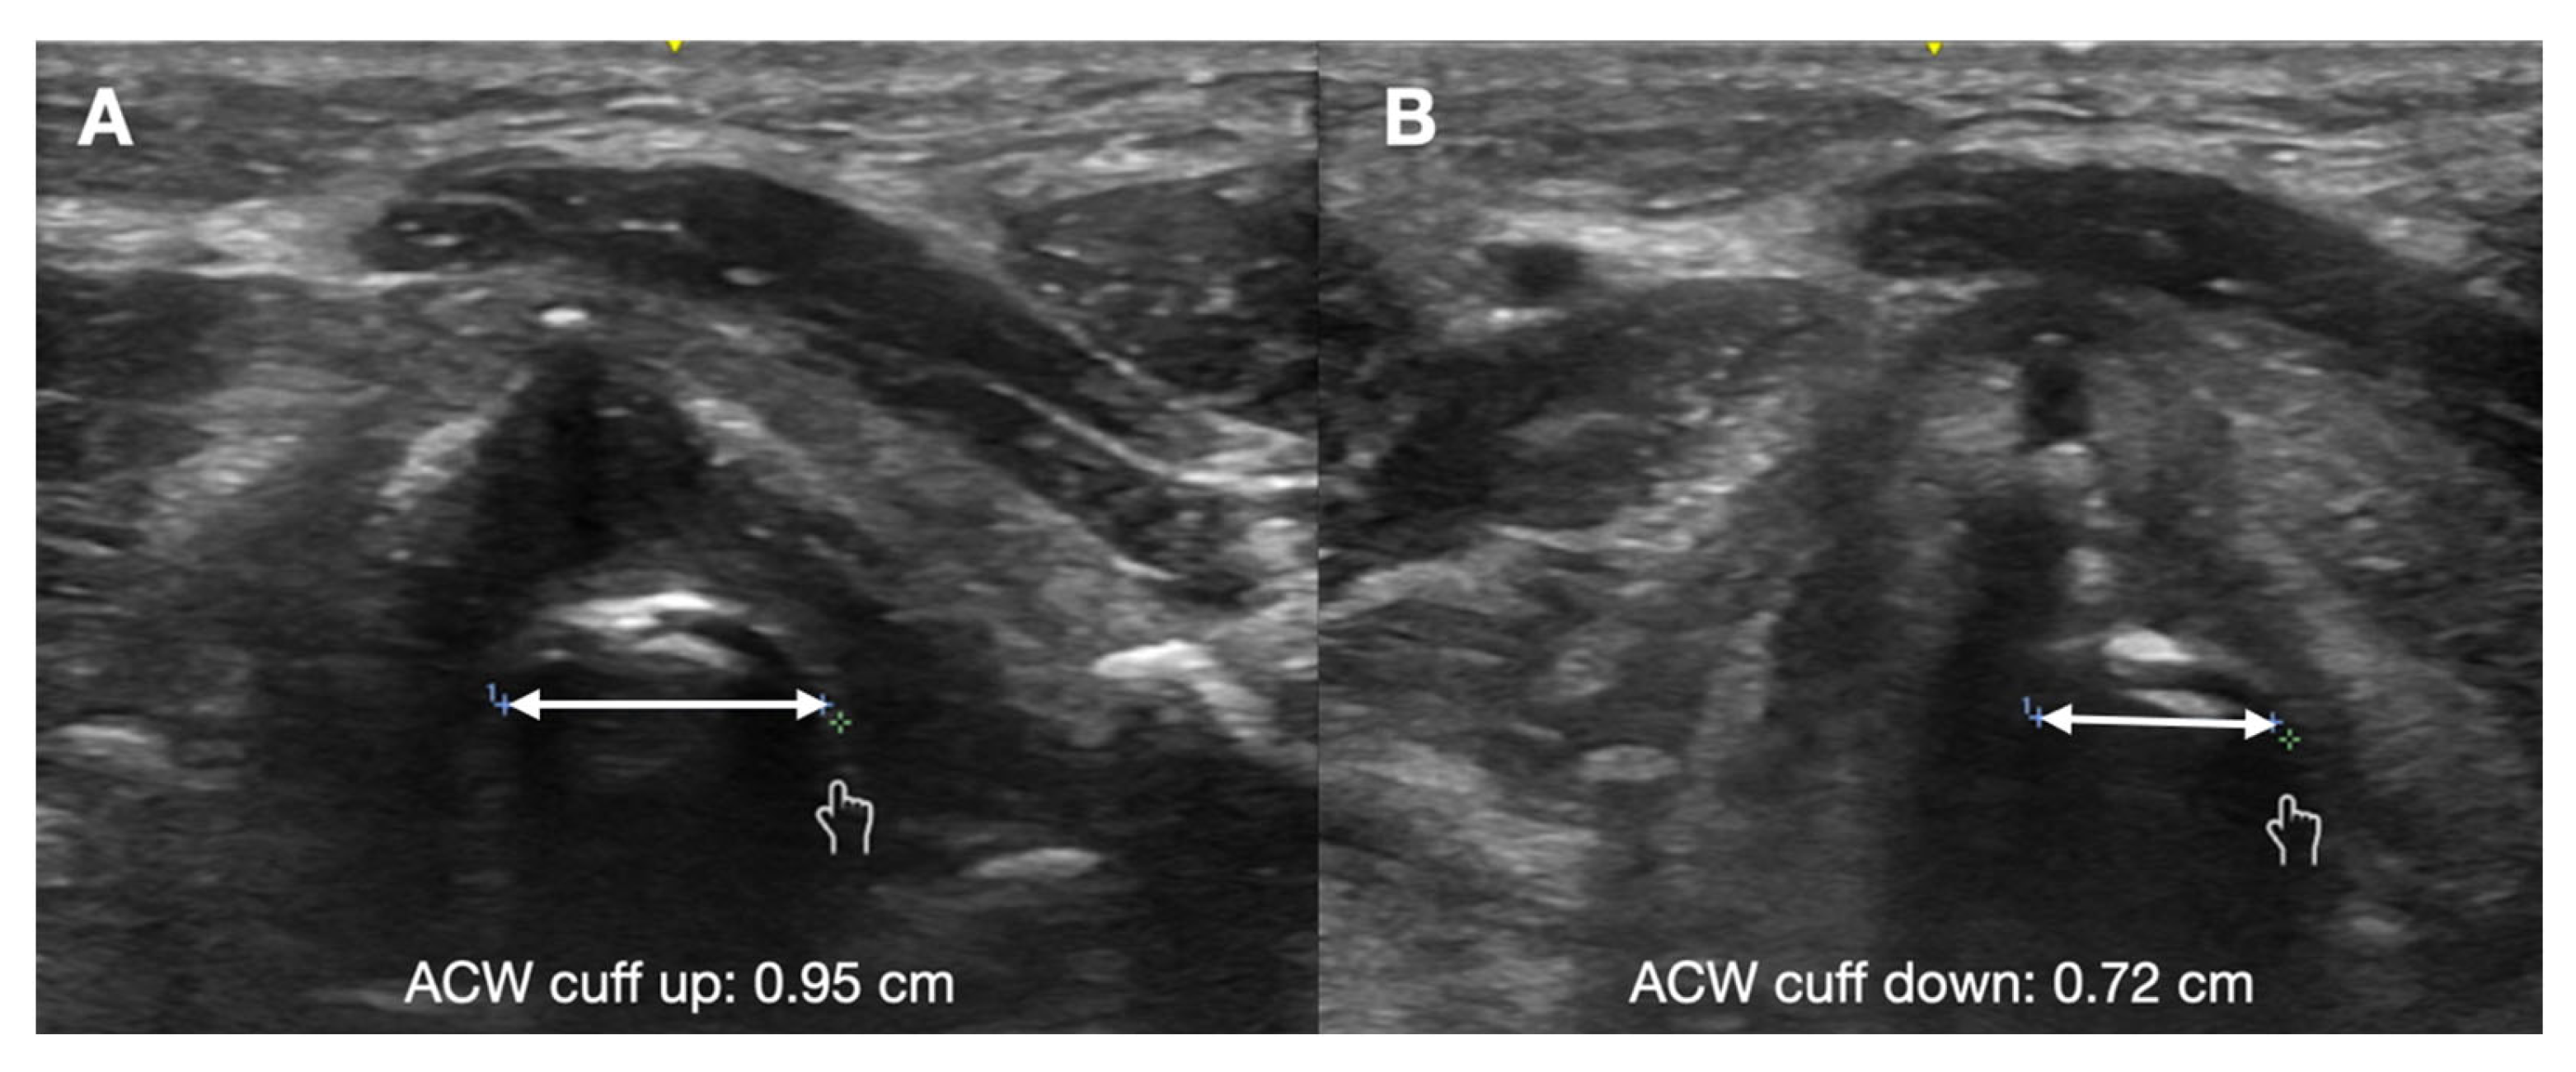

- Mikaeili, H.; Yazdchi, M.; Tarzamni, M.K.; Ansarin, K.; Ghasemzadeh, M. Laryngeal ultrasonography versus cuff leak test in predicting postextubation stridor. J. Cardiovasc. Thorac. Res. 2014, 6, 25–28. [Google Scholar]

- El Amrousy, D.; Elkashlan, M.; Elshmaa, N.; Ragab, A. Ultrasound-Guided Laryngeal Air Column Width Difference as a New Predictor for Postextubation Stridor in Children. Crit. Care Med. 2018, 46, e496–e501. [Google Scholar] [CrossRef]

- Ding, L.W. Laryngeal ultrasound: A useful method in predicting post-extubation stridor. A pilot study. Eur. Respir. J. 2006, 27, 384–389. [Google Scholar] [CrossRef] [PubMed]

- El-Baradey, G.F.; El-Shmaa, N.S.; Elsharawy, F. Ultrasound-guided laryngeal air column width difference and the cuff leak volume in predicting the effectiveness of steroid therapy on postextubation stridor in adult. Are they useful? J. Crit. Care 2016, 36, 272–276. [Google Scholar] [CrossRef]

- Bhargava, T.; Kumar, A.; Bharti, A.; Khuba, S. Comparison of Laryngeal Ultrasound and Cuff Leak Test to Predict Post-Extubation Stridor in Total Thyroidectomy. Turk. J. Anaesthesiol. Reanim. 2021, 49, 238–243. [Google Scholar] [CrossRef] [PubMed]

- Tsai, W.W.; Hung, K.C.; Huang, Y.T.; Yu, C.H.; Lin, C.H.; Chen, I.W.; Sun, C.K. Diagnostic efficacy of sonographic measurement of laryngeal air column width difference for predicting the risk of post-extubation stridor: A meta-analysis of observational studies. Front. Med. 2023, 10, 1109681. [Google Scholar] [CrossRef] [PubMed]